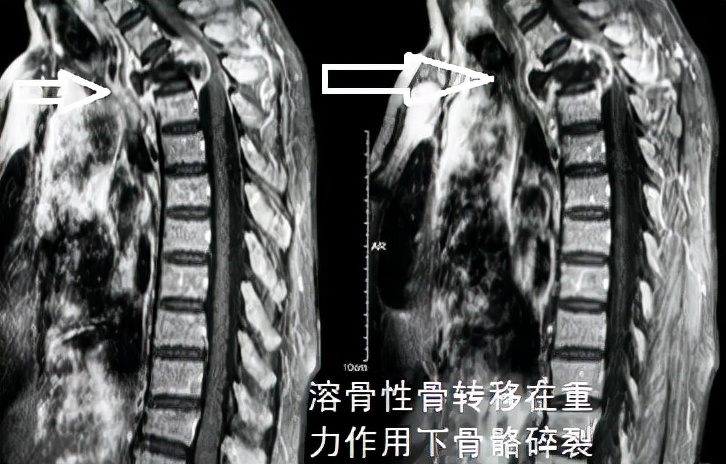

Of course, bone metastasis is not without risks; it can sometimes be very dangerous. For example, as shown in this image, a compression fracture due to thoracic spine metastasis can lead to paralysis.